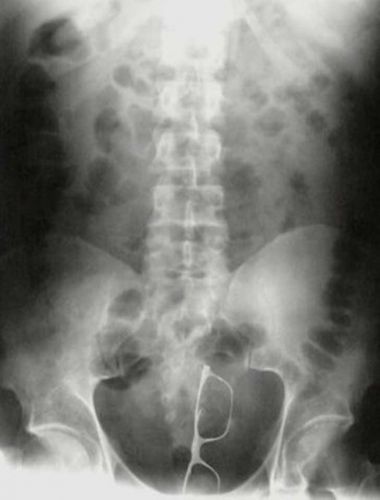

© Reprodução

Óculos